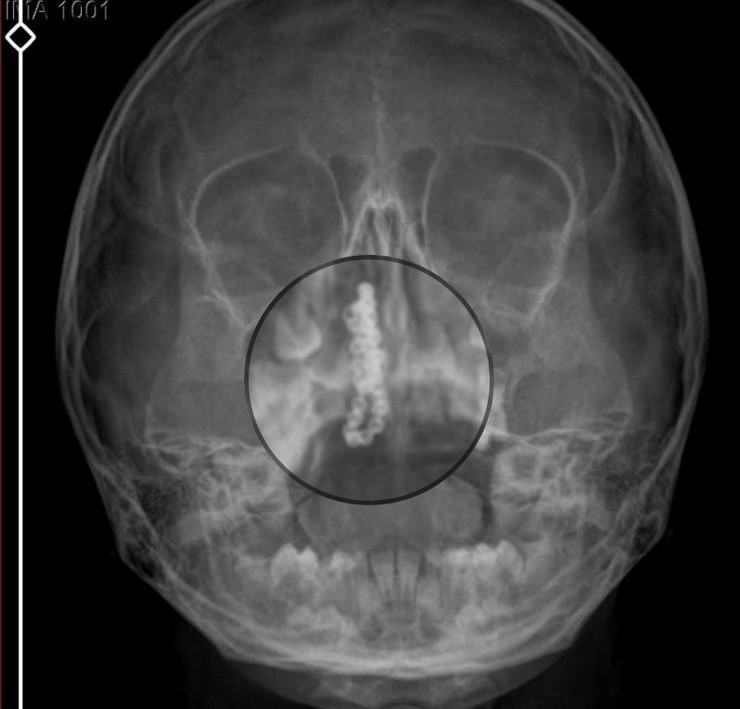

Kentte yaşayan Gökhan-Nalan Tekin çifti, yaklaşık 4 ay önce şiddetli burun kanamasının yanı sıra akıntı şikayetleriyle kızları Polen'i, bir özel hastaneye götürdü. Burada röntgeni çekilip, tetkikleri tamamlanan küçük kıza, iddiaya göre enfeksiyon teşhisi konulup, ilaç verildi. Eve dönen aile, kanama ve akıntının geçmemesi üzerine bu kez Rize Devlet Hastanesi'ne başvurdu. Devlet hastanesindeki doktorun incelemesi ve kapsamlı röntgen çekilmesi sonrası Polen'in burnunda metal cisim olduğu fark edildi. 2 yıldır burunda kaldığı değerlendirilip, küçük top şeklinde tırnak makası zinciri olduğu belirlenen cisim, başarılı ameliyatla çıkarıldı. Bir süre tedavisi sürdürülen Polen, sağlığına kavuşunca taburcu edildi. Özel hastane yetkilileri, konuyla ilgili açıklama yapmazken; aile suç duyurusunda bulunacaklarını söyledi.

Kızının burnundan sürekli siyah renkte akıntı olduğunu anlatan Gökhan Tekin, "Çocuğumun burnundan kanama ile sürekli siyah akıntı geliyordu. Özel hastaneye götürdüm. Özel hastanede film çekildi, hiçbir bulguya rastlanılmadığı söylendi. O siyah leke de enfeksiyona dayalı olan bir şey olduğu bize söylendi. Eve geldik, akıntı sürmesi üzerine bu kez devlet hastanesine başvurduk. Burunda metal zinciri fark ettiler. Böyle bir ihmalkarlık olabilir mi? Özel hastaneye gidiyoruz, paramızla rezil oluyoruz. Zincir, 2 yıldır burnunda ve devletimizin hastanesinde iyi bir doktorumuz zinciri ortaya çıkarıyor, kızım ölümden dönüyor. Ben sonuna kadar bu işin peşini bırakmayacağım. Sonuna kadar hukuk mücadelesi vereceğim. Bu da diğer hastalarımıza ibret olsun. İşte, bakın koca bir zincir. 'Bulguya rastlanılmadı' deniliyor" dedi.

Kızının ameliyat sonrası durumunun iyi olduğunu söyleyen Tekin, "İnanır mısınız bize 'Evde soba mı yanıyor? Acaba kömür isten dolayı mıdır bu?' dendi. Böyle bir şey olabilir mi? Ameliyattan çıkan parmağım kadar zincir. Devlet hastanesindeki doktor da 'Bu nasıl gözden kaçılabilir? Böyle bir pozisyon nasıl görülmeyebilir?' yorumunda bulundu. Allah'a şükür olsun atlattık. Şu anda durumu, vaziyeti iyidir. Ben şuna inanıyorum doktor da bir şans işidir. Bakın paramızla özele gideriz ya hani bizde, daha iyi ilgilenirler. Oysa devlet hastanesindeki doktorumuz olayı meydana çıkardı" diye konuştu.